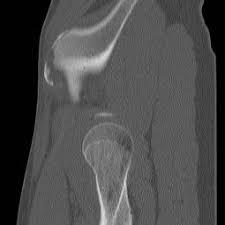

Timely, accurate diagnosis is imperative so proper treatment can be initiated. Ebraheim's educational animated video describes the condition of avulsion fractures around the hip in adolescence. Call 999 and ask for an ambulance. I was doing high jump and twisted my body and in the process my muscle ripped my growth bone off. Hip fractures are classified according to their anatomical location as intracapsular, which involves the femoral head and neck, and extracapsular, which includes intertrochanteric, trochanteric, an. With an avulsion fracture, an injury to the bone occurs near where the bone attaches to a tendon or ligament. Symptoms of ankle avulsion fracture are similar to ankle sprain. Call your health care provider if your pain doesn't go away, or if you notice swelling. Preparing for an avulsion fracture in the ankle? Avulsion fractures of the hip and. Avulsion fracture of the iliac crest is an uncommon pathology. This happens when a muscle or tendon connected to the hip bone suddenly tightens so hard that it pulls off part of the bone. I am 15 and did it to my hip/ upper pelvic bone.

With an avulsion fracture, an injury to the bone occurs near where the bone attaches to a tendon or ligament. Anyone can suffer an avulsion fracture of the ankle, but athletes and children are more prone to them than the rest of us. This happens when a muscle or tendon connected to the hip bone suddenly tightens so hard that it pulls off part of the bone. Ebraheim's educational animated video describes the condition of avulsion fractures around the hip in adolescence. An avulsion fracture occurs when a small chunk of bone attached to a tendon or the hip, elbow and ankle are the most common locations for avulsion fractures in the young athlete. If you think you've fractured your hip, you'll need to go to hospital as soon as possible. In acute avulsion fractures, there is usually a clear preceding traumatic incident. When to seek medical help. The causes of hip fracture are very different in young and elderly patients. With age, the bones can become weak and brittle. Other causes include cancer and injury. They usually happen when a bone is moving one way, and a tendon or ligament is suddenly pulled the opposite way. Hip apophyseal injuries in young athletes are a fairly rare problem, and often go unrecognized by health professionals.

Pain in the hip area may be referred from the knee joint or from structures in the inguinal canal, testis (including torsion) and lower abdomen, or from the lower back. Teenagers are more likely to have this injury than younger children. The causes of hip fracture are very different in young and elderly patients. Other causes include cancer and injury. Hip fracture occurs in approximately 341,000 persons in the united states each year. Read about causes, treatment options, available mobility devices, tips for recovery, and more. This happens when a muscle or tendon connected to the hip bone suddenly tightens so hard that it pulls off part of the bone. In acute avulsion fractures, there is usually a clear preceding traumatic incident. A hip fracture is a break in the bones of your hip. A hip fracture is a common injury, especially in people with osteoporosis. I was doing high jump and twisted my body and in the process my muscle ripped my growth bone off. A broken hip in older people is often partly the result of weakening bones from osteoporosis. This most commonly occurs at the ischial tuberosity where the hamstrings attach, or the iliac pain at the bony part on the front of the hip may be an anterior superior iliac spine avulsion fracture.